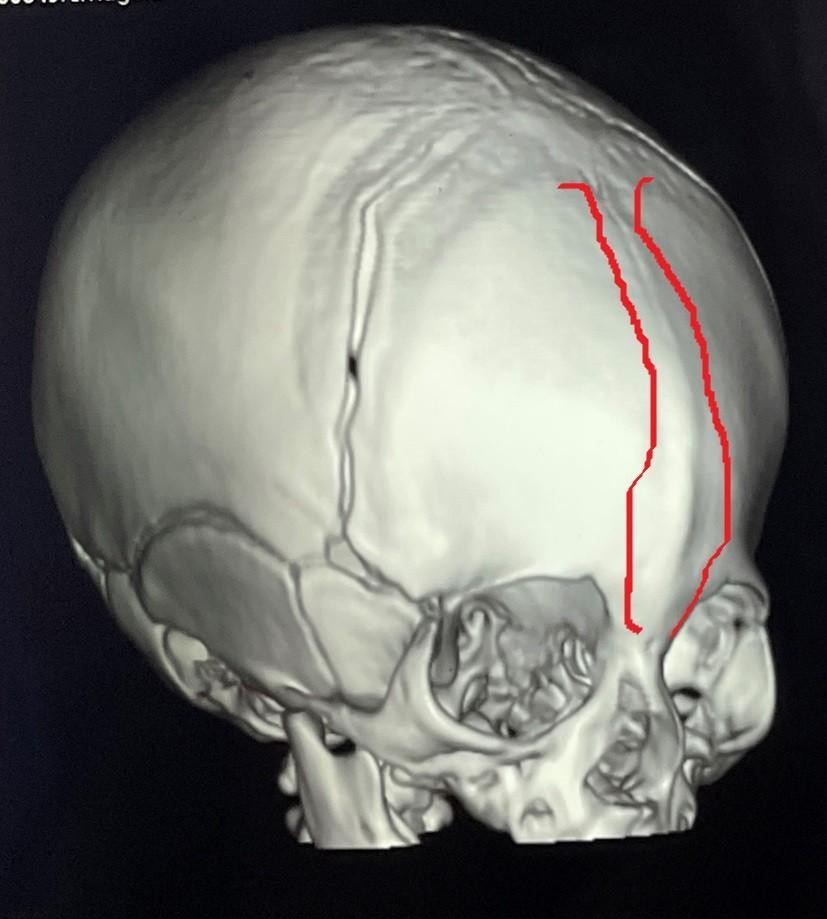

تم إجراء جراحة تقويم ناجحة لطفل يبلغ من العمر شهرين كان يعاني من حالة تعرف باسم "الرأس المثلث". هذا النوع من التشوهات الجمجمية يؤدي إلى ظهور الرأس بشكل مثلثي مع وجود نتوء بارز في الجبهة. الهدف من الجراحة كان تصحيح شكل الجمجمة لضمان النمو الطبيعي للدماغ وحماية الطفل من المشاكل المستقبلية.

• تخطيط دقيق مسبق باستخدام التصوير ثلاثي الأبعاد